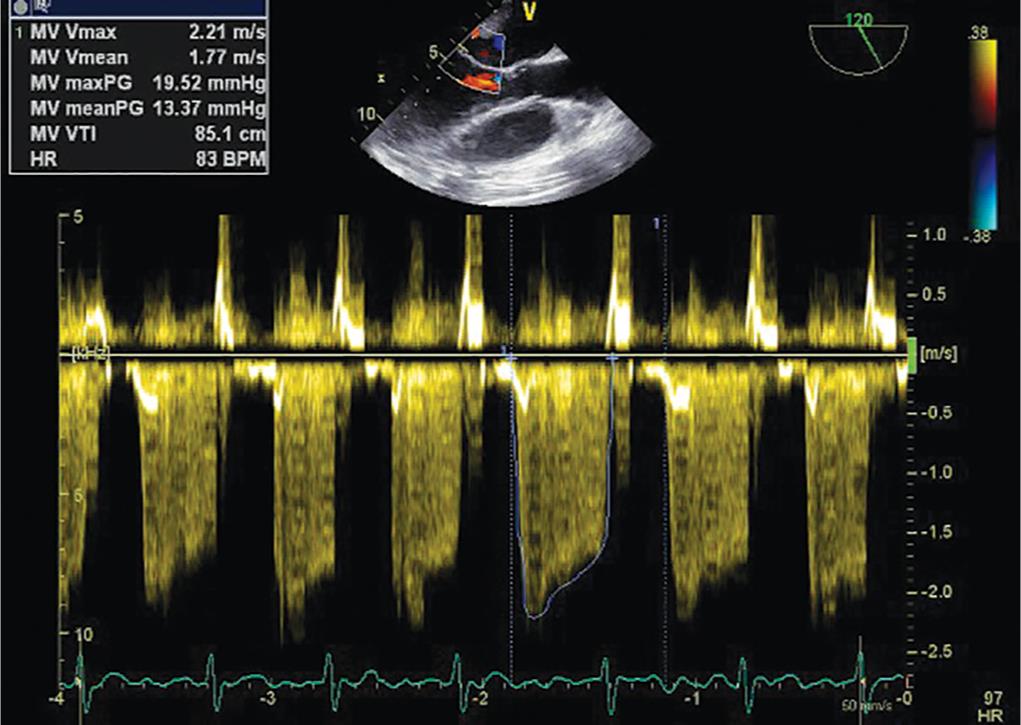

A 35-year-old male patient came to our institute with a chief complaint of palpitations and grade IV dyspnoea for the last 6 hours. His blood pressure was 80/50 mm Hg and had an irregularly irregular pulse with a rate of 154/minute. On auscultation, a low-pitched grade III mid-diastolic murmur was heard at the mitral area in addition to bilateral basal crepitation. Electrocardiography showed AF with a rate of 152/minute. Transthoracic echocardiography (TTE) revealed a bi-atrial enlargement, dilated right ventricle, and a large (59 × 40 mm) mobile hyperechoic mass in the LA originating from interatrial septum which is prolapsing into the left ventricle in diastole (Figs 1A and B and Video 1). Color Doppler echocardiography revealed an increased flow velocity across the mitral valve during diastole and severe tricuspid regurgitation (TR). Right ventricular systolic pressure (RVSP) was estimated as 58 mm Hg + central venous pressure (CVP) from TR jet (Fig. 2). Tricuspid annular plane systolic excursion of the lateral wall of the tricuspid annulus was 9 mm, suggesting a severe RV dysfunction. Because of LA myxoma and grade IV dyspnea, the patient was taken for excision on an emergency basis. In the operating room after attaching the standard American Society of Anesthesiologists monitoring, an arterial line was placed in the left radial artery, a 7-French triple lumen, central venous catheter was placed in the right internal jugular vein. Anesthesia was induced with 200 μg fentanyl and 60 mg ketamine. Muscle relaxant was achieved with 6 mg vecuronium and the trachea was intubated with 8-mm endotracheal tube. Transesophageal echocardiography (TEE) probe (6VT; GE Healthcare; Vivid e9; Norway) was inserted, and the TTE findings were confirmed (Figs 1C and D). Continuous-wave Doppler placed across the mitral valve revealed a mean gradient of 13 mm Hg (Fig. 3). Anesthesia was maintained with isoflurane and with intermittent doses of vecuronium. Ventilator management was adjusted to maintain PCO2 between 30 mm Hg and 35 mm Hg and PaO2 between 100 mm Hg and 150 mm Hg. A large mass of 60 mm × 64 mm × 42 mm was successfully excised under cardiopulmonary bypass (CPB). After adequate rewarming, we tried coming off CPB with inotropic support of milrinone 0.6 μg/kg/minute, noradrenaline 0.1 μg/kg/minute, and adrenaline 0.1 μg/kg/minute. However, we could not maintain the blood pressure and the CVP raised up to 20 mm Hg. Transesophageal echocardiography showed a severe RV dysfunction with severe TR with RVSP of 65 mm Hg and CVP of 17 mm Hg (Fig. 4 and Video 2). Pulmonary artery pressure (PAP) was measured by a 26-G needle and found to be near systemic. The CPB was again initiated and inhaled nitric oxide (iNO) was started at 20 ppm in the inspiratory limb of the ventilator to prevent RV failure. After 20 minutes, the patient was successfully weaned off from CPB with stable hemodynamics. In the postoperative period, oral sildenafil was started at a dose of 0.5 mg/kg three times a day. As hemodynamics were stable with a cardiac index of 2.5 L/minute/m2, RVSP of 40 mm Hg and CVP of 6 mm Hg, iNO was tapered after 48 hours. Extubation of trachea was done 24 hours after stopping iNO, and it was uneventful. Later on, inotropic agents were reduced and stopped, and the patient was shifted to ward from the intensive care unit (ICU) after 7 days without any complication. Transthoracic echocardiography revealed a moderate RV dysfunction with good left ventricular (LV) systolic function before discharge. During the ICU stay, there were no episodes of AF, and the methemoglobin concentration never exceeded 0.9%.

Fig. 3: A continuous wave Doppler placed across mitral valve in midesophageal long axis view showing a mean gradient of 13 mm Hg in diastole